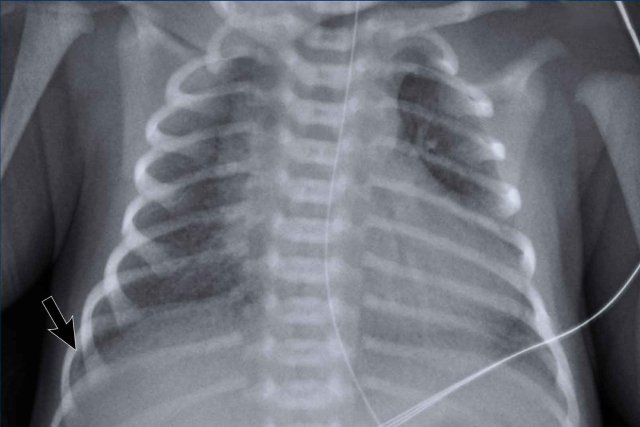

Premature, 28 weeks of gestational age treated for RDS.

Blood via the tracheal tube.

Image

• Patchy opacifications in the right lung, due to hemorrhage.

• Atelectasis of the left lower lobe (arrow) with mild hyperinflation of the left upper lobe.

• Good position of ETT.

• Low position of umbilical vein line, NG tube in situ.